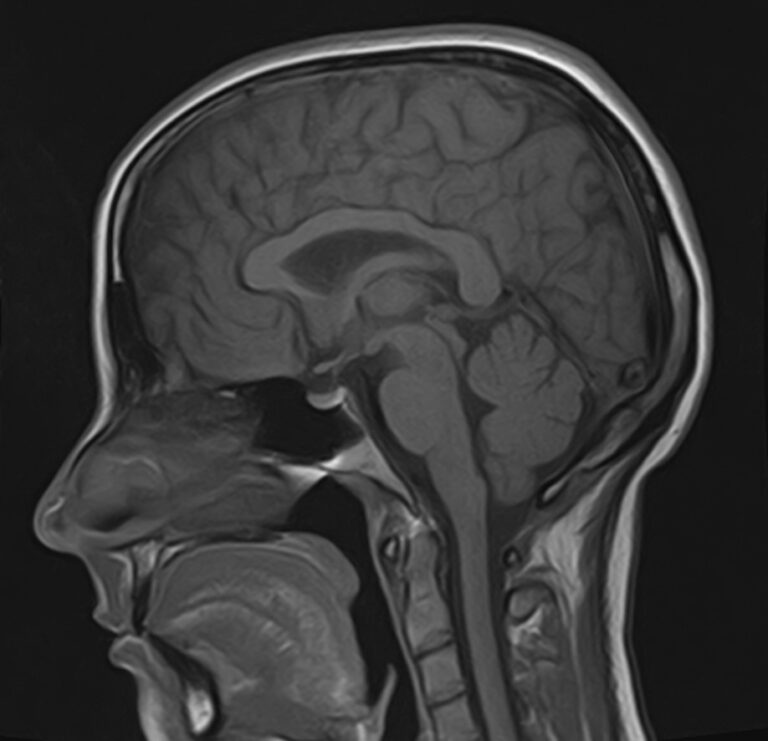

В клинике «Доступная медицина» можно пройти комплексное обследование, включающее в себя два протокола сканирования близко расположенных друг от друга анатомических областей – шейного отдела позвоночника и головного мозга. Метод комплексного обследования оценивает состояние всех структур головного мозга и самого верхнего сегмента позвоночного столба, который включает в себя 7 шейных позвонков, спинной мозг с отходящими от него нервными корешками и окружающими мягкими тканями.

Сканирование проводится на современном высокопольном магнитно-резонансном томографе закрытого типа TOSHIBA VANTAGE TITAN 1,5 Тесла. Магнитно-резонансный томограф производит послойное сканирование исследуемой зоны в разных плоскостях, затем при помощи компьютерных программ преобразует полученные данные в трехмерные изображения с высокой степенью детализации.

Что показывает МРТ головного мозга + шейного отдела позвоночника

В рамках проведения данного комплексного исследования можно выявить:

• очаги ишемического и геморрагического инсульта, область поражения, признаки отека головного мозга, стадию развития заболевания;

• доброкачественные и злокачественные новообразования, их точную локализацию, стадию развития процесса, проводить динамическое наблюдение за опухолевым процессом на фоне лечения;

• признаки демиелинизирующих заболеваний (рассеянный склероз), выявить очаги поражения миелиновой оболочки нервных волокон, определить стадию заболевания;

• характерные признаки дегенеративных заболеваний головного мозга (болезнь Альцгеймера, старческая деменция, болезнь Паркинсона), определить изменения коры головного мозга и подкорковых структур;

• поражение структур головного мозга на фоне травм, гематомы головного мозга;

• изменения, характерные для психических расстройств различного генеза (эндогенных и экзогенных), после вирусных инфекций, черепно-мозговых травм, отравлений токсическими веществами, на фоне наследственных заболеваний;

• остеохондроз, спондилоартроз, спондилез, межпозвонковые грыжи, унковертебральный артроз, сколиоз, усиленный или выпрямленный лордоз как нарушение статической функции позвоночника, травмы, аномалии позвоночника.